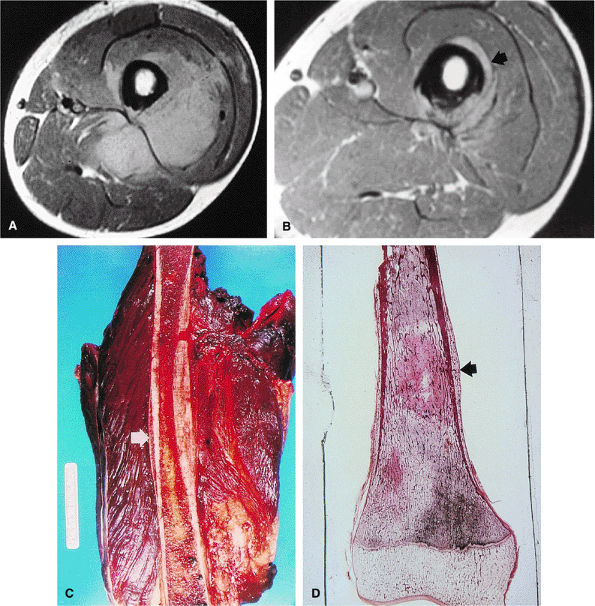

FIGURE 14-70 ● (A) A T2-weighted sagittal image shows osteosarcoma involving the femoral metaphysis (small arrows). Bright contrast portions of the high-signal-intensity tumor represent necrosis with hemorrhage (large arrow). (B) The corresponding gross specimen shows central tumor necrosis (arrow). (C) Macrosection of amputated specimen cut in the coronal plane displaying a large extracortical tumor mass with various tissue types, including young tumor osteoid at the outer edge (short arrow) contrasting with malignant chondroid tissue (curved arrow) that would demonstrate higher signal on T2-weighted images. The long arrow indicates Codman—s reactive triangle. (Reprinted with permission from

(Fig. 14-70). The major cause for failure is stress shielding secondary to stem loosening. This is avoided in newer systems with more compliant, stress-sharing fixation devices.